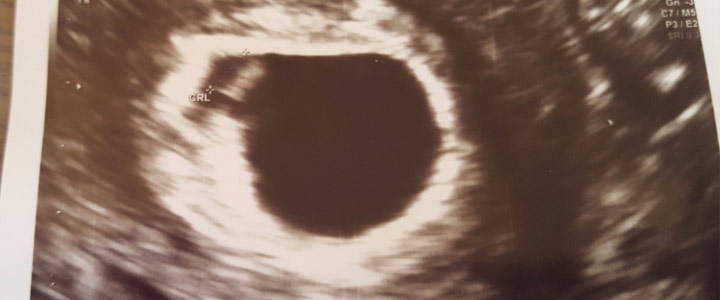

Spannende echo van drieling met een vergrote blaas

De dag van de echo ‘U kwam voor een echo?’ Klopt mevrouw! ‘U mag gaan liggen.’ Ik begon mijn broek uit te trekken, weet ik veel dat het al uitwendig kon. Na alle onderzoeken in het Flevoziekenhuis ...

Op de echo naar drie babys kijken